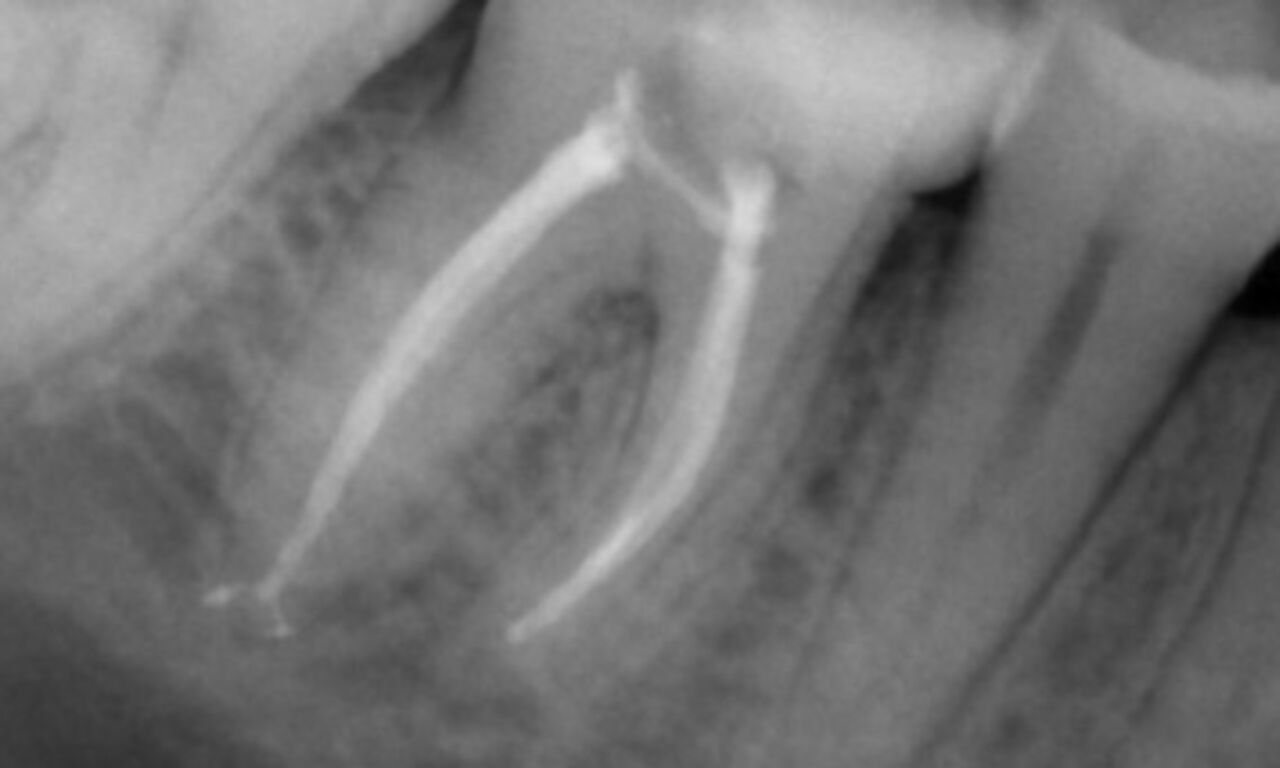

Periapical radiolucency associated primarily with the distal root and loss of lamina dura on the mesial root.

TruNatomy was chosen in this case to allow a caries leveraged approach and a focus on pericervical dentin preservation especially on the mesial aspect where the tooth had a more minimal restoration.

"A patient and process centered success."

Dr. Cowie